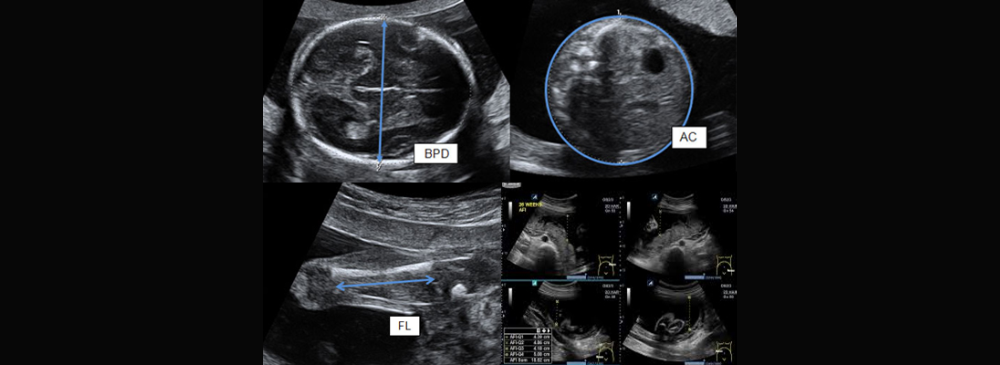

During a growth scan, our radiologists applies a warm, safe ultrasound gel to your abdomen and uses a probe to capture images of the baby. The scan typically lasts 20–30 minutes and is completely non-invasive. Our team checks the baby’s head, abdomen, and femur measurements to estimate weight and growth rate. The scan also evaluates amniotic fluid, placental position, and umbilical cord blood flow.